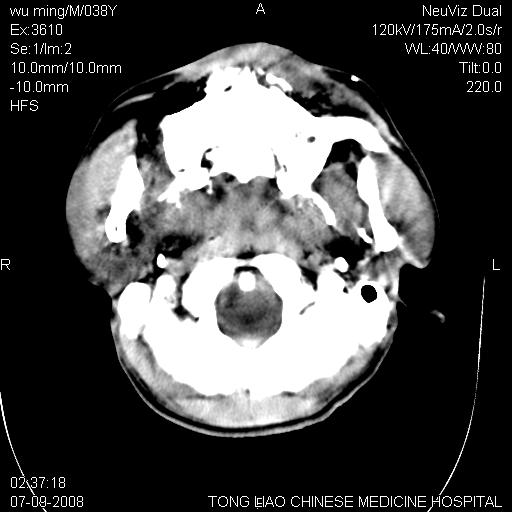

考虑:面骨、颅底骨多发骨折,颅内高压(脑肿胀)。

面骨、颅底骨多发骨折,右侧硬膜下小血肿,弥漫轴索损伤,死亡原因可能是多种因素致。

1)颅底骨及颌面骨多发性骨折。2)副鼻窦及双侧鼻腔积血。

颅底骨折,窦腔内积血。考虑死亡原因为脑水肿压迫脑干或因大量失血死亡。

前颅窝颅底骨折,死的原因应该从头部来看不用说就是重度颅脑损伤。